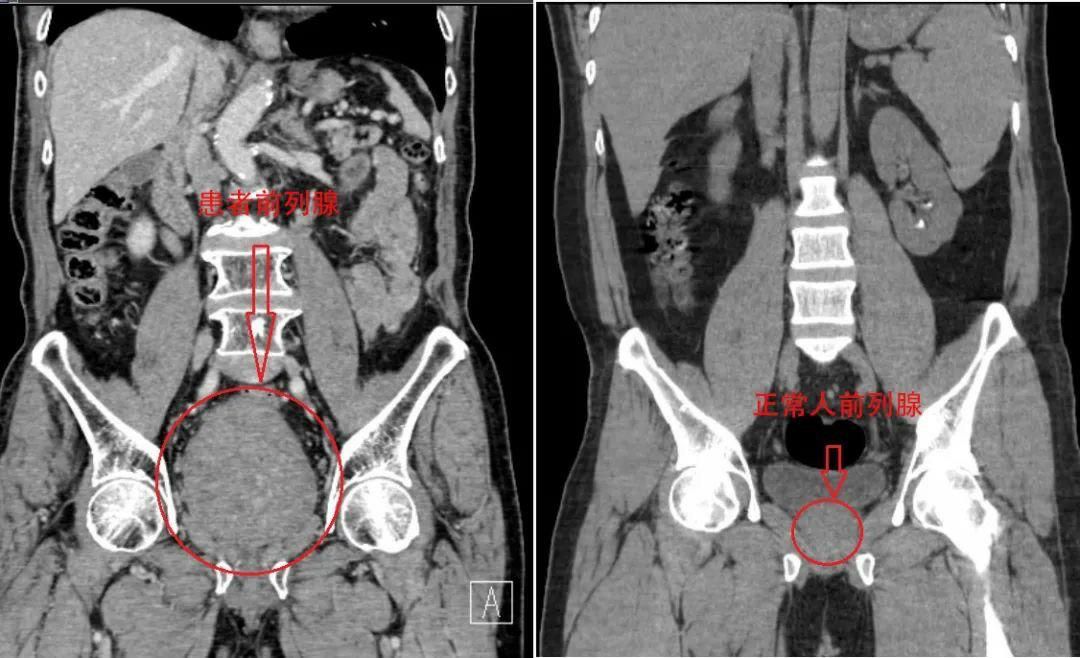

据了解,正常前列腺重量约20g,而李大爷的前列腺重量达到惊人的400g,增重近20倍。然而,能解决李大爷痛苦的方法有两种选择,一种是通过膀胱造瘘或者长期留置尿管,这种方案虽然简单,但是今后的生活及护理极不方便,会给患者造成很大的心理负担;另一种就是将增生的前列腺用钬激光“切掉”,经过抉择后李大爷选择进行手术。